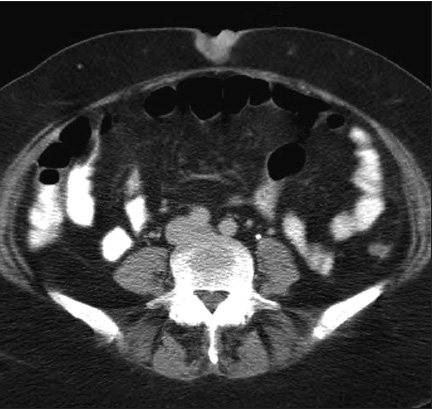

Imaging studies revealed replacement and enlargement of the uterus, with a mass that traversed ordinary tissue boundaries and planes (Figure 1). In concert with the histopathological appearance of biopsy material, positive studies for estrogen and progesterone receptors on the same secured the diagnosis of a primary endometrial adenocarcinoma. Metastatic spread to navel was vividly demonstrable as well (Figure 2).

![]() |

| Figure 2 – The umbilical nodule is readily seen on this more cranial cut of the CT as the radiodense bump in the fat external to the stripe of abdominal wall musculature, in the midline at the top of the image, ending at the level of the otherwise narrow strip of skin. Anterior surface of the Sister Mary Joseph nodule (superior here) shows 2 irregular bumps, but given the ordinary crevasses of the navel, this would not raise concerns were the clinical story innocuous and the navel more ordinarily radiolucent. Radiolucency just posterior to the nodule confirms only that no direct extension is present at this craniocaudal level. Air-fluid levels are seen in loops of bowel that contain oral contrast agent. The abdomen here lacks the “frozen [pelvis] full of tumor” seen in the prior image. To my non-radiologist eye, no cancer is detectable on this image apart from the umbilical nodule. |